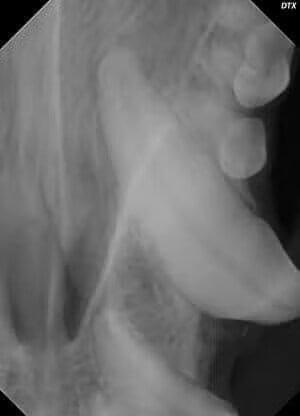

Any chipped or discolored tooth may have a root canal (endodontic) problem. They are usually diagnosed on the physical exam after the heavy tartar is removed and when an abscess is seen at the tip or apex of the tooth on a radiograph.